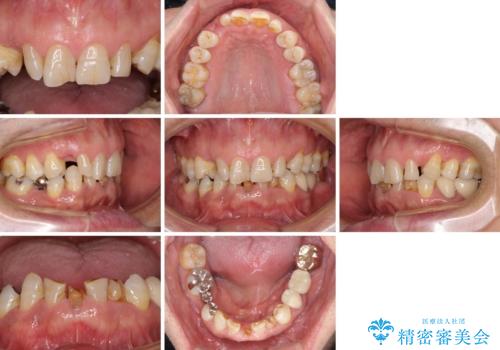

- 乳歯や矮小歯が多くある前歯部の審美障害が気にして来院された患者様です。

上顎の矮小歯は隙間が多く、歯軸の傾斜も大きかったため、部分矯正により補綴治療前に歯の位置を整えることとしました。

下顎の乳歯は支台歯として機能することは困難と思われたので、事前に抜歯をし、上顎の矯正治療終了のタイミングに合わせて、セラミックブリッジにて補綴治療することとしました。

前歯部はディープバイトという、上顎前歯が下顎前歯に深く覆い被さる咬合であったので、理想的には全顎矯正が必要となりますが、今回は患者希望により前歯部のみの部分矯正で対応しました。そのため下顎犬歯の神経を取り除くことになってしまったのは心残りであります。